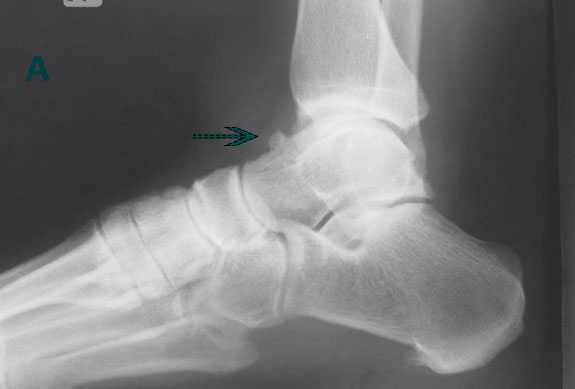

А, На рентгенограмме в боковой проекции виден тыльный остеофит таранной кости.

В, МР-томограмма с признаками объемного образования кпереди от сухожилия передней большеберцовой мышцы.

Разрывы сухожилия передней большеберцовой мышцы чаще всего локализуются в пределах 2-3 см от точки его прикрепления.

Причиной разрыва может быть дегенерация сухожилия вследствие длительно существующего импинджмента, вызванного остеофитами таранно-ладьевидного, ладьевидно-клиновидного и плюснеклиновидного суставов, либо контактом с удерживателем разгибателей.